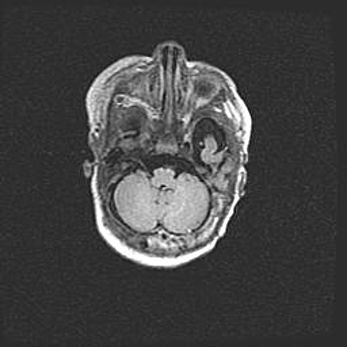

Мальформация Денди-Уокера. Киста задней черепной ямки.

Агенезия мозолистого тела.

Возраст: 2,5 месяца

Вес: 2420 г

Пол: женский

Окружность головы: 37 см

Срок гестации: 32 недели

Мальформация Денди—Уокера — редкий вид патологии ЦНС, представляющий собой врожденный порок развития каудального отдела ствола и червя мозжечка, ведущий к неполному раскрытию срединной (Мажанди) и латеральных (Лушка) апертур IV желудочка мозга. Для этогно синдрома характерна триада симптомов: гипотрофия червя мозжечка и/или полушарий мозжечка, кисты задней черепной ямки, гидроцефалия различной степени. В 70% случаев порок сочетается и с другими аномалиями головного мозга, в частности с агенезией мозолистого тела.